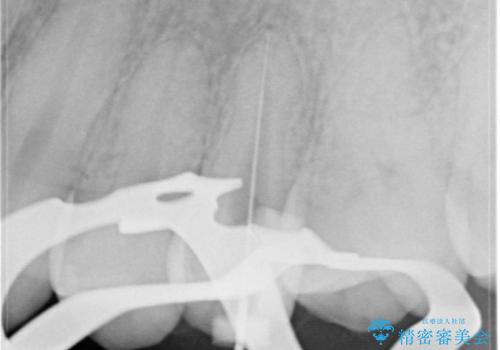

根管治療〜オールセラミッククラウン

- 奥歯がズキズキ痛いことを主訴に来院されました。

根管治療を行なったのち、オールセラミッククラウンにて修復治療を行なっております。

根管治療を行なった歯は速やかに歯冠修復が必要です。